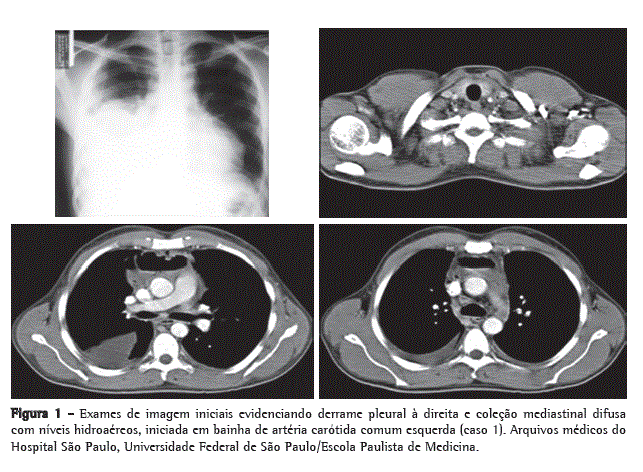

Admitido na urgência, apresentava-se ao exame físico hipocorado (2+/4+), taquipneico (22 ciclos/min), normotenso (110 × 60 mmHg), com edema e flogose cervical, macicez à percussão da base do HTD, murmúrio vesicular abolido no terço médio e inferior do HTD, taquicardia (124 bpm), mas sem alterações à ausculta cardíaca. Exames gerais mostraram leucocitose (16.900/µL), com 9% de bastões e 81% de neutrófilos, plaquetose (756.000/µL), proteína C reativa e VHS elevadas (225,9 mg/L e 92 mm/h). Na radiografia de tórax, evidenciamos alargamento mediastinal superior, opacidade dos dois terços inferiores de HTD e aumento de área cardíaca. O paciente então foi submetido à TC cervicotorácica, que evidenciou coleções volumosas com conteúdo gasoso iniciando na região cervical, seguindo pela bainha carotídea esquerda e estendendo-se para o mediastino anterior e médio, pericárdio e cavidade pleural direita (Figura 1).